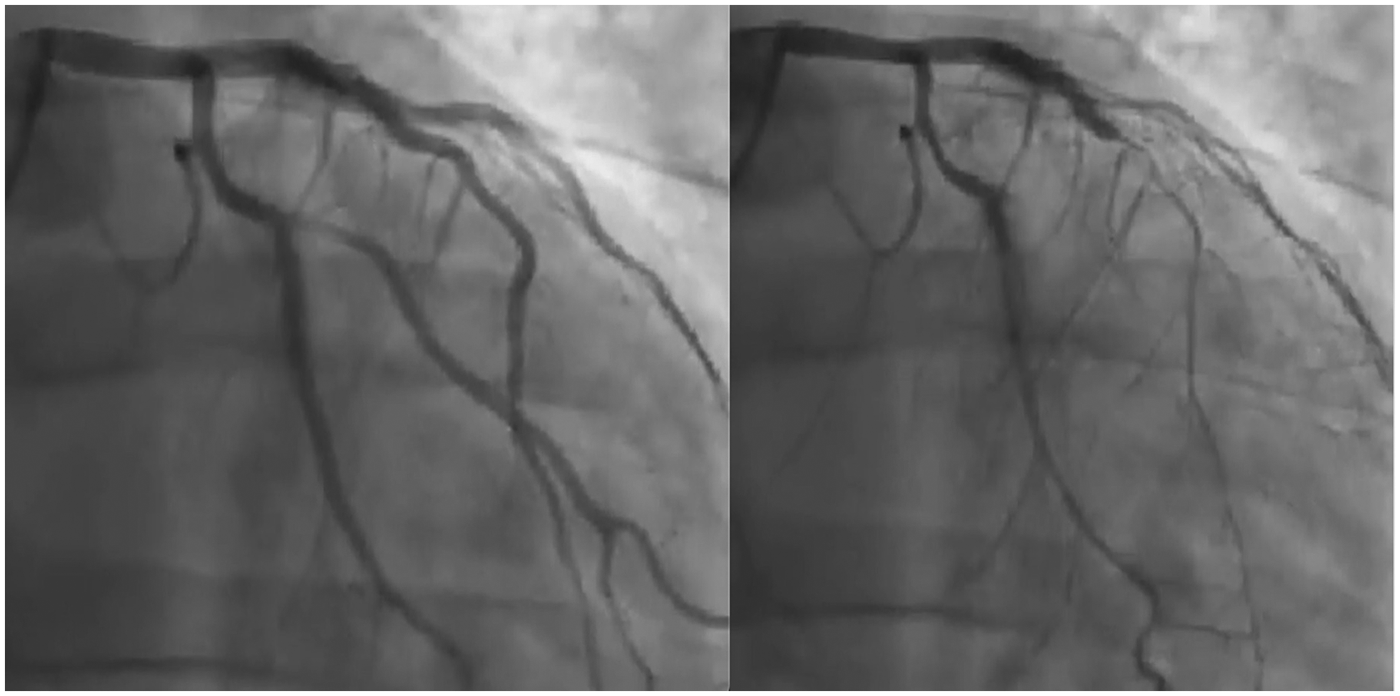

Despite maximal medical therapy, the patient continued to report disabling chest pain. Initial antiplatelet therapy consisted of aspirin in combination with clopidogrel and was later switched to ticagrelor, given evidence that ticagrelor exhibits more positive effects on endothelial dysfunction than other antiplatelets. These effects are linked to its ability to raise adenosine levels, leading to activation of NO synthase, reduced inflammation, and improved vascular function. In December 2021, intracoronary acetylcholine testing provoked severe, diffuse spasm of the LAD, which resolved after nitrate administration (Supplementary Video 1 and Figure 2), confirming a diagnosis of epicardial vasospasm. The patient described pain during the test, although his ECG showed no significant changes.

Figure 2

Left anterior descending artery injection before (left panel) and after (right panel) acetylcholine infusion.